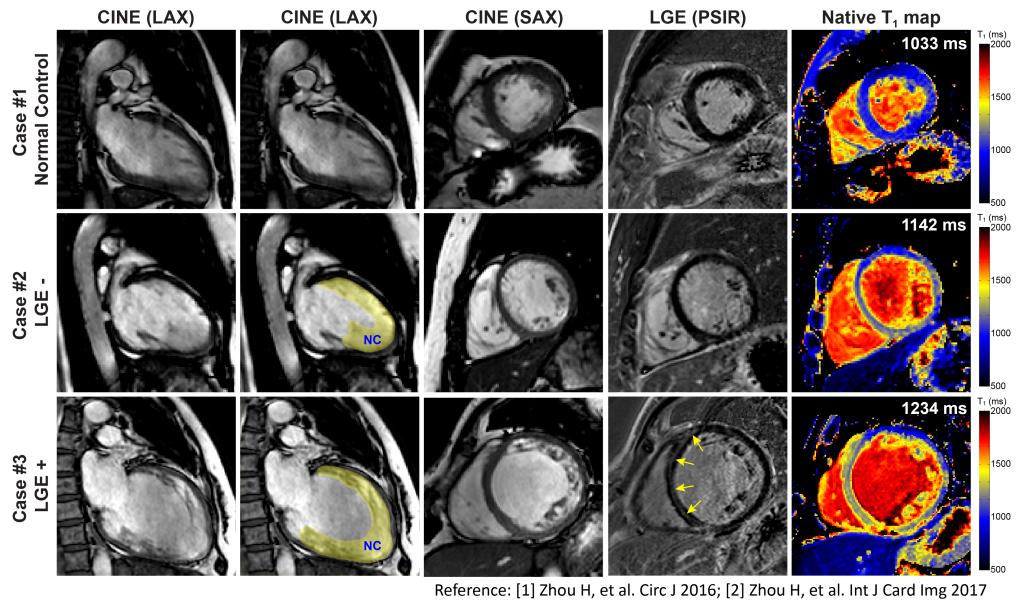

心脏磁共振T1、T2定量技术

左心室心肌致密化不全心肌病中病人的分层